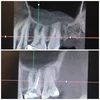

تسوس الأسنان

أمراض الأسنان واللثة

كيسات الفك